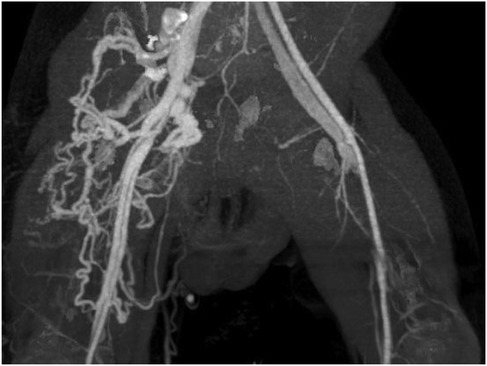

Background: Congenital arteriovenous fistulas (AVFs) are rare, particularly those involving the bilateral femoral arteriovenous system in an infant. This case report details the successful management of this condition using a combined therapeutic approach. Case Presentation: We report the case of a 6-month-old boy who presented with a congenital bilateral femoral arteriovenous fistula, which led to symptoms of fatigue, shortness of breath, and recurrent pneumonia. The patient was successfully treated with a combined therapeutic approach of surgical ligation on the left side and endovascular coil embolization on the right. At the 10-year follow-up, the patient's clinical and echocardiographic status remained normal. The imaging surveillance protocol included regular duplex ultrasound examinations, which confirmed sustained occlusion of both fistulas with no residual dilated veins in the right thigh. The patient remains asymptomatic with no evidence of recurrence. Conclusion: This case highlights the importance of a tailored, combined-modality approach for complex congenital AVFs, especially when the fistulas on each side possess different anatomical characteristics. The specific morphology of the fistula is a critical determinant in choosing the optimal treatment strategy to ensure complete closure and prevent long-term complications such as high-output cardiac failure. This approach serves as a valuable clinical reference for the management of similar complex vascular anomalies in the pediatric population.